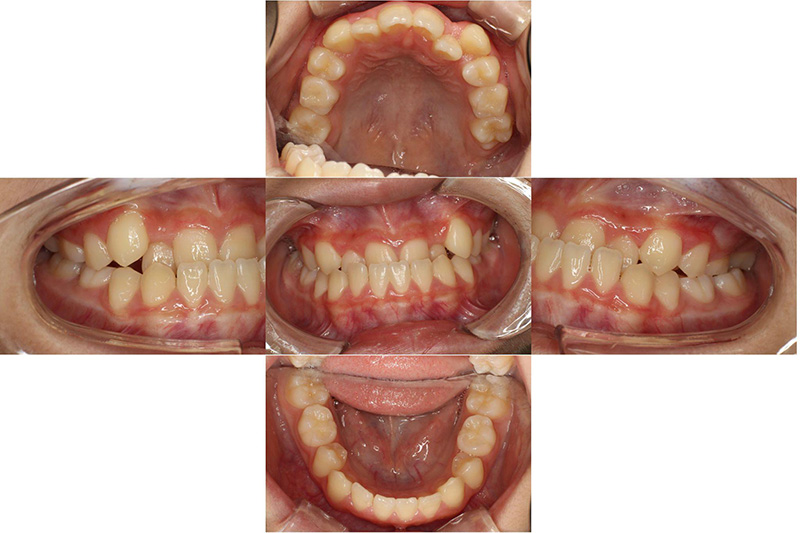

治療前

治療後

| 治療内容 | プレオルソタイプ3を日中1時間と夜間就寝時装着それに加え口腔周囲筋のトレーニング |

|---|---|

| 治療期間・回数 | 約12ヶ月、10回 |

| 費用 | 約11万円 検査費用含む |

| 副作用リスク | 後戻り 歯の痛み 歯の動揺 咬合違和感 |